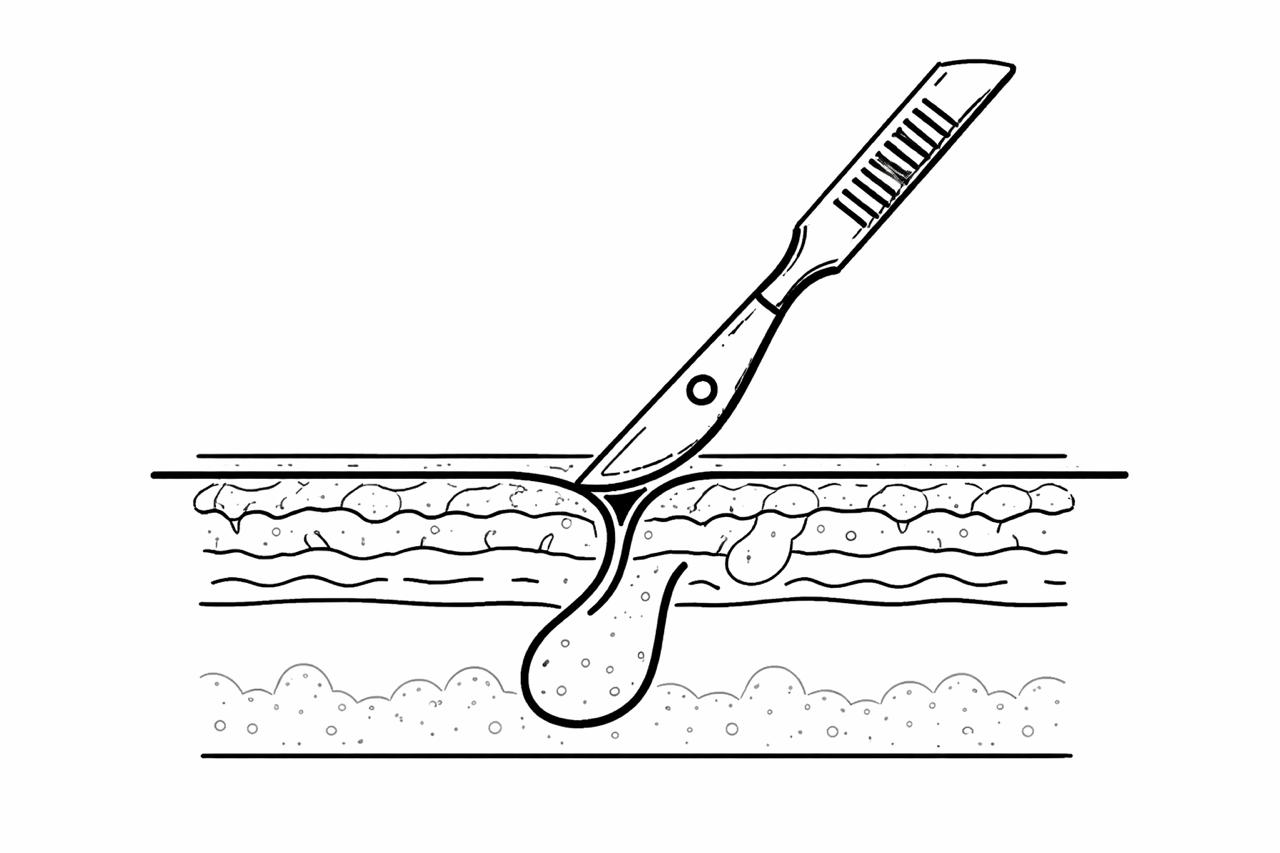

Lipoma Removal Surgery

Quick surgical removal of lipoma ensuring minimal pain and faster recovery.

Abscess Drainage Surgery

Surgical drainage of abscess removing infection and relieving severe pain.